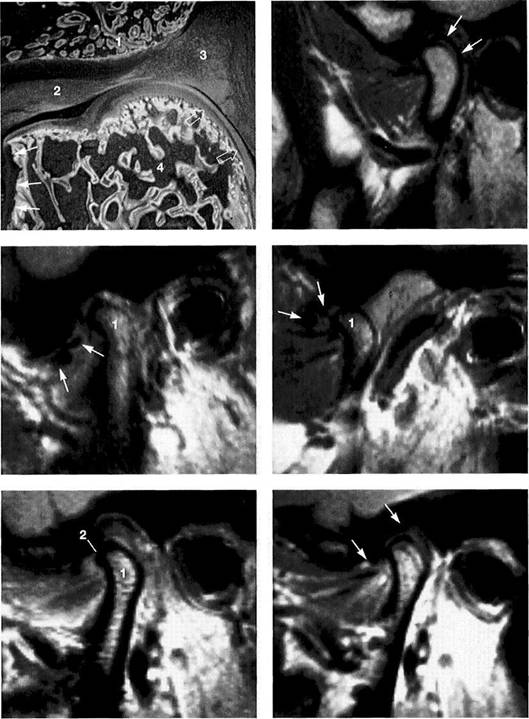

Normal joint

Left: Macroscopic anatomical pre­paration of a right temporo­mandibular joint with normal disk position. The pars posterior (1), pars anterior (2), pars media (arrow), and condyle (3) can be clearly seen.

Right: In spite of the reduction in signal caused by formalin fixation, the corresponding slice in MRI shows the identical relationships between the disk (1,2) and condyle

Medial disk displacement

Left: Formalin-fixed preparation from a right joint. In this anterosu-perior view, the displacement of the disk (arrows) toward the medial is evident.

Lateral pterygoid muscle

Lateral pole

Medial pole

Right: MRI in the angled coronal plane confirms the medial disk po­sition (arrows). The contours of the fossa and condyle are reproduced precisely.

Shape of the pars posterior

Left: Macroscopic anatomical pre­paration of a right articular disk showing its positional relationship to the condyle. The posteroinferior edge of the pars posterior (1) shows a small triangular area of fi­brosis (arrows).

Right: In spite of the sharply re­duced signal emission resulting from formalin fixation, even this type of change is accurately repro­duced (arrows). Here the use of a combination of T1 and T2 weight­ing is often helpful.

Reproduction of Anatomical Detail in MRI

Fibrosis of the bilaminar zone

Left: Formalin-fixed preparation of the centromedial part of a left tem­poromandibular joint with localized fibrosis of the bilaminar zone (ar­rows).

Pars posterior

Right: The MRI accurately repro­duces the abnormality (arrows) dis­tal to the flattened pars posterior. The contour of the condyle is indi­cated by a broken line.

Presumed "posterior disk displacement"

Left: Macroscopic preparation of a left temporomandibular joint with normal positioning of the pars an­terior (1) and pars posterior (2) in the lateral portion of the joint. The retrodiskal structures appear thick­ened.

Right: In an MRI there appears at first glance to be a posterior disk displacement (arrows). Under clos­er inspection, however, it can be seen that the pars anterior (1) and pars posterior (2) lie in correct rela­tion to the condyle.

Left: A view of the disk and the bil­aminar zone after further prepara­tion again reveals the correct posi­tional relationships. Here the pars anterior (1) and pars posterior (2) can be identified more readily. The presumed "posterior disk displace­ment" is a false positive interpreta­tion of the fibrosis of the bilaminar zone (arrows).

Right: MRI of the same joint shown in Figure 427.

Disk perforation and osteoarthrosis

Left: Anatomical preparation of a left temporomandibular joint with arthrotic changes (black arrows) and extensive disk perforation (white arrows). In the anterior re­gion only a part of the former pars anterior (1) can still be recognized.

Right: MRI shows similar conditions. The cortical layer of the arthrotic condyle is thickened extensively (arrows). The remainder of the pars anterior (1) can still be distin­guished.